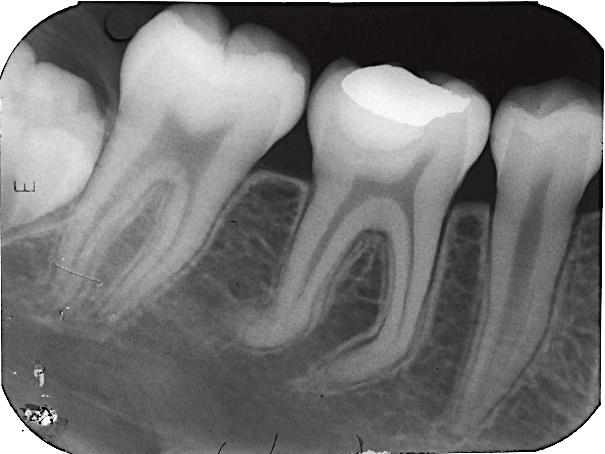

8.Biodentine®AnalternativeinVitalPulpTherapyinYoungPermanentTeeth.ClinicalCase,40monthFollow-Up. (Pgs.88-96)

Biodentine®UnaalternativaenlaTerapiaPulparVitalenDientesPermanentesJóvenes.CasoClínico.Seguimientode40Meses.

LuisDavidRamosFlores,DDS,